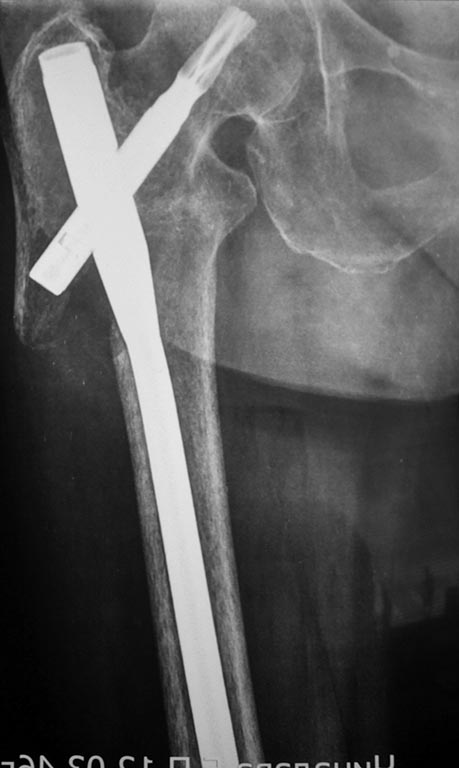

Здравствуйте уважаемые коллеги.Прошу поделиться своим опытом,мнениями, для помощи в анализе данного клинического случая. Пациентка К. 80лет,вес ок 90 кг.с сопутствующей соматической патологией большинства пациентов данной возрастной группы. Оперирована PFN-a long. Анализируя результаты Ro,напрашивается следующее: 1.Латеральный вход- "-". 2.Вальгус позиция -"+". 3.Расположение клинка высоко - "-". Какова вероятность несостоятельности фиксации при данной комбинации? Будет ли стабильнее фиксация при более дистальномрасположении клинка,но при отсутствующей латеральной стенке? Спасибо!

Ни угол в гвозде, ни мнимое или реальное отсутствие латеральной стенки здесь ни при чем. Проблема обусловлена латеральной точкой введения и медиальным направлением в центральном отломке. На приложенной картинке зеленым обозначено должное положение.